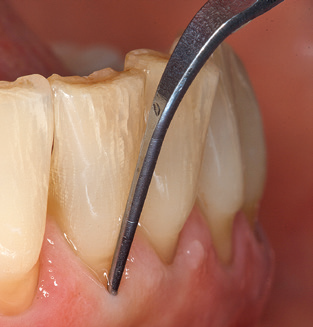

Fig. 4: Flexible probes with millimetre markings are recommended for the probing of dental implants (e.g. Colorvue Kit PCV11KIT6, Hu­Friedy). – Fig. 5a and b: A straight working tip (1P, W&H Dentalwerk Bürmoos GmbH) is a suitable instrument for use on all natural teeth. – Fig. 6: Curved working tips (3Pr/3Pl, W&H Dentalwerk Bürmoos GmbH) lend themselves to the processing of difficult-to-reach areas of the tooth and root surfaces (e.g. furcations). – Fig. 7: The tapered, hexagonal implant cleaning tip (1I, W&H Dentalwerk Bürmoos GmbH) permits atraumatic and efficient cleaning of the crown and abutment surfaces. – Fig. 8: Titanium and carbon curettes are suitable instruments for the manual cleaning of the implant surfaces.

Following machine cleaning of the tooth and implant surfaces, the surfaces of the natural teeth are cleaned manually using standard hand instruments. When performing manual cleaning, particular attention must be given to maintaining the correct angle of application, appropriate sharpness, good support and working with the curette from apical to coronal. Either titanium or carbon curettes should be used for post-cleaning of the implant structures (Fig. 8). In addition to the use of ultrasonic devices, power jet devices can also be used in conservative dentistry. However, it must be taken into consideration that these procedures are not suitable for removing hard deposits and thus they cannot replace the use of hand instruments and ultrasonic instruments completely. In all cases, cleaning is followed by mechanical polishing of the accessible tooth and implant surfaces with polishing cups and polishing compounds (Fig. 9).